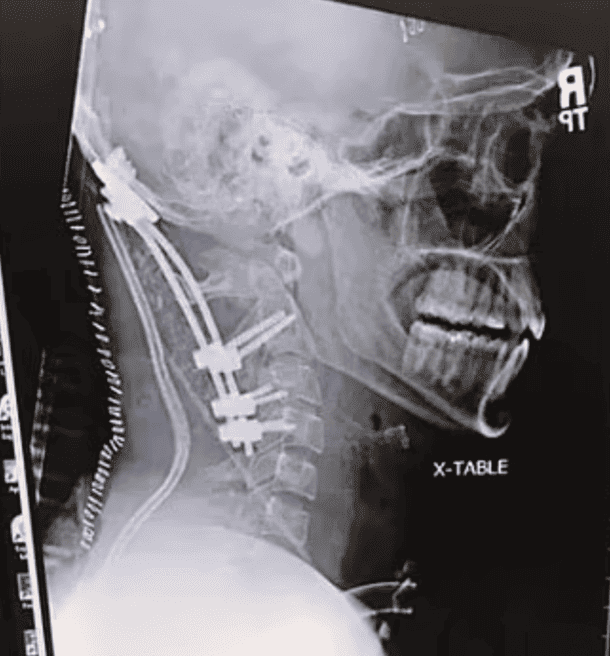

Un agriculteur américain de 50 ans, victime d’un accident en 2020, a survécu à une AOD de type 1 avec rupture complète des ligaments apical et alaire, ainsi que de l’odontoïde. Il a subi une arthrodèse occipito-cervicale, puis porté un collier rigide durant 18 semaines. Sa convalescence, documentée sur Reddit, est remarquable : malgré une perte de 50 % de mobilité cervicale, aucune séquelle neurologique majeure n’est à déplorer.

La procédure de référence est la fusion occipito-cervicale postérieure, utilisant des vis occipitales, des crochets translaminaires et des tiges en titane. Elle vise à stabiliser la jonction cranio-rachidienne et prévenir toute lésion secondaire de la moelle épinière.